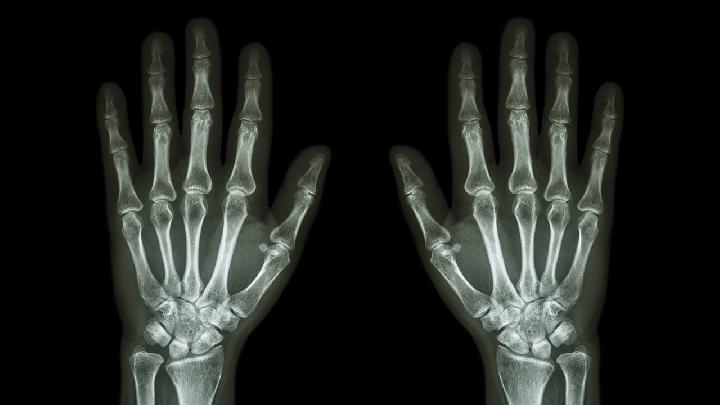

类风湿性关节炎怎么检查呢,这个问题大家有必要来了解一下,才能在疾病来临的时候不感到那么迷茫,生活中总会发生一些我们不想看到的事情,疾病就是存在我们心中的一大疾病,但是,这样的情况又是我们没有办法避免的情况,对于类风湿关节炎的发生您知道有什么检查的方法吗,接下来我们就来详细的了解一下吧。